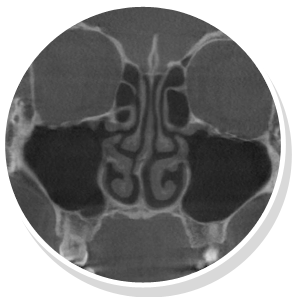

비중격만곡증 비정상